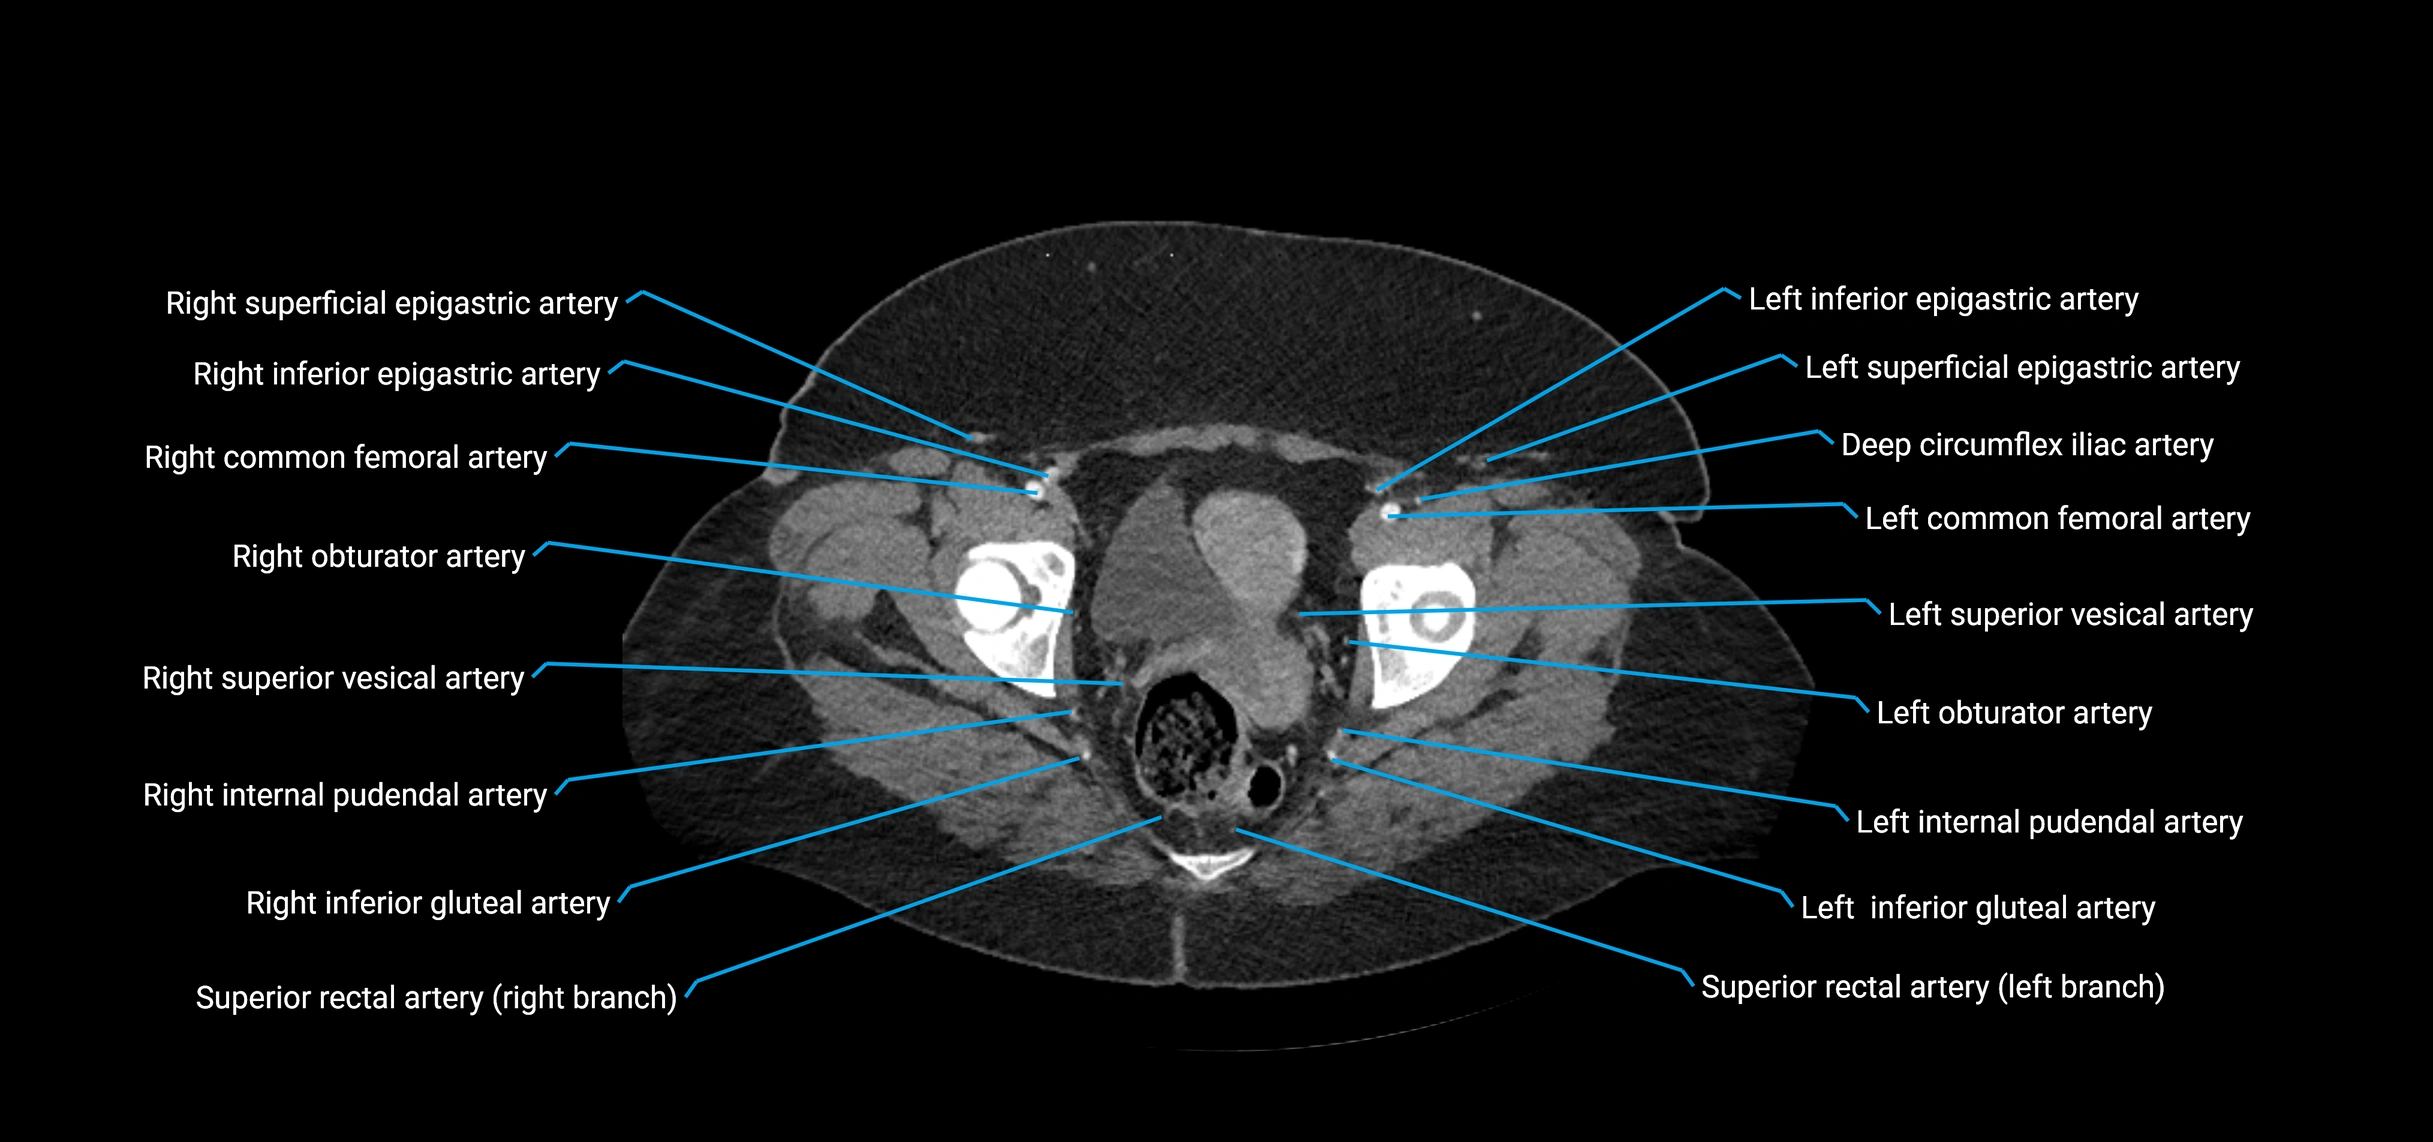

Contrast-enhanced CT (CTA):

• Gold standard for abdominal aortic imaging

• Provides excellent detail of lumen, wall, aneurysm, thrombus, and branch vessels

• Multiplanar and 3D reconstructions help in aneurysm measurement, stent graft planning, and dissection evaluation